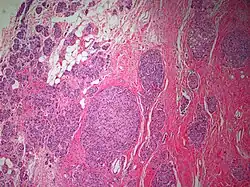

The microscopic histopathology of PACB tumors prepared with hematoxylin and eosin staining shows that >90% of the tumors consist of apocrine gland-like tissue. The lesions must also show that tumor cells have broken through their ducts of origin to invade adjacent tissue in at least one area. Most of the tumor cells (termed type A cells[15]) typically appear somewhat more irregular than normal apocrine gland cells. They have abundant eosinophilic (i.e. pink due to the uptake of the eosin dye) cytoplasm which contain numerous granules[11] and large mitochondria.[15] Their nuclei are large, variably sized and shaped, have multiple nucleoli (which are eosinophilic[11] and may be distinctively large in size[14]), and are surrounded by highly visible nuclear membranes. The cells are arranged into solid sheets, nests, papillae, and/or cords (see Figs. 1 and 2).[11] The tumor cells' cytoplasmic granules test positive when treated with the PAS diastase stain.[16] Binucleated cells, i.e. cells with two nuclei, are common.[10] Less commonly, type B apocrine cells are present; these cells have a more foamy and vacuolated cytoplasm (i.e. containing multiple vacuoles) than type A cells[15] and often resemble foamy histiocytes or sebaceous gland cells.[17] The tumor cells have low to moderate rates of proliferation based on their Ki-67 protein levels.[7] PACB tissues may have localized areas that contain mucin-like secretions within their luminal ducts,[10] localized areas of necrosis (i.e. foci containing dead or dying cells), and/or microcalcifications spotted throughout the apocrine tissue.[11] The stroma (i.e. connective tissue between the sheets, nests, papilla and cords of cells) typically contains non-malignant, infiltrating lymphocytes (see Fig. 3). In an examination of 41 PABC tumors, 33 (80.5%) had <50% of their stroma tissues infiltrated with these cells while 8 (19.5%) had ≥50% of their stroma tissues infiltrated with them. Tumors with ≥50% of their stroma infiltrated with lymphocytes tended to have carcinoma cells that had high rates of proliferation.[11] Metastatic and recurrent PACB tumors have a histopathology similar to their original primary tumors.[14]